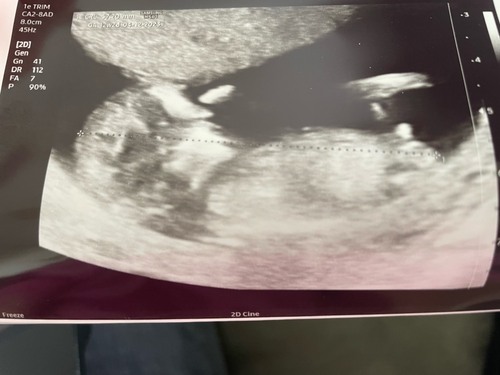

Iemand een idee? Termijn 12,2😊

Volgensmij staat de nub in een hoek, en dat betekend een jongen😊